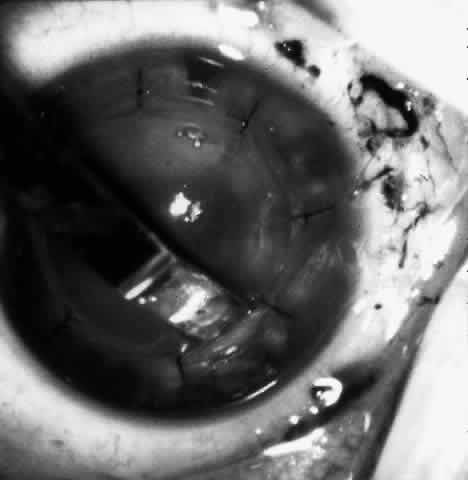

Sixteen to 22 interrupted 10-0 nylon sutures are placed to secure the edge of the lens in the peripheral corneal stroma trough. The first eight sutures are placed with the edge of the lens lying over the circular trephine mark (Fig. 10). As with any corneal transplant surgery, the second suture is the most important in centering the lens. All knots must be tied in such a way that the knots may be buried easily. At the same time, the sutures must not be tightened so tightly that compression occurs with the lens. My personal preference is for a 2-1-1 surgeon's knot. Care should be taken to prevent the lens from being sewn eccentrically into the bed, to prevent astigmatism. After the first eight sutures are placed, the edge of the lens is tucked into the stromal bed all around (Fig. 11) and the remaining 8 to 14 sutures are placed to fasten the lens securely in place (Fig. 12). The sutures are rotated so that the knots are buried in the recipient cornea. This allows the surgeon to remove the sutures at a subsequent examination under anesthesia (EUA) by means of traction directed peripherally without dehiscence of the wound.

Fig. 10. Lenticule is sutured with interrupted 10-0 nylon sutures.

Fig. 11. After the first eight sutures are in place, the edges of the lenticule are tucked into the bed.

Fig. 12. The remaining eight sutures are placed with the lenticule edges tucked.